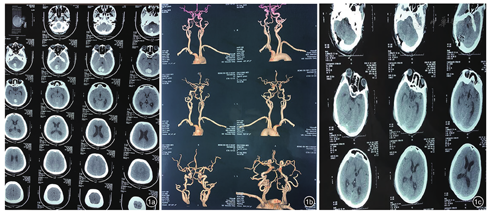

患者女性,42岁,因突发头痛、头晕5天,加重半天于2019年9月26日收住我院神经内科。既往体健。查体见神志清,言语流利,脑神经检查未见异常,颈部有抵抗感,四肢肌力5级,双侧腱反射对称(++),病理反射未引出,深浅感觉检查正常。颅脑CT:小脑见团块状高密度影,占位效应明显,第四脑室下部受压变窄,余脑室扩大,考虑小脑出血(图1a)。头颈部CTA:左侧胚胎性大脑后动脉,余未见明显异常(图1b)。血生化检查:无高血脂及高胆固醇。会诊后认为:小脑出血诊断明确,出血量约13 ml,第四脑室受压,有轻度脑积水表现,手术指征明确,建议行小脑出血开颅清除术。患者及亲属3天后同意手术,全麻下以血肿为中心做后枕部旁正中直切口,颅骨铣骨瓣成型,上方暴露至横窦下缘,硬脑膜张力高,"十"字切开硬膜,皮层造瘘直达血肿腔,血肿主体为褐色血性液体,夹杂部分凝固血块,清除血肿后,见血肿腔有黄白色珍珠样新生物及钙化,有包膜,血运极不丰富,新生物及钙化约占整个血肿的1/3,清除所有新生物,并留取标本行病理检查。术后复查CT较满意(图1c)。常规病理:镜下见出血坏死组织,伴钙化及胆固醇结晶形成,局部见微量短梭形细胞,细胞性质及类型待定;免疫组化结果:短梭形细胞Vimentin(+),GFAP(+),CD56(+),Syn(+),NSE(+),结合颅脑CT的出血性表现考虑为小脑陈旧性出血、坏死组织伴含铁血黄素沉着、钙化及胆固醇结晶性肉芽肿形成(图2)。